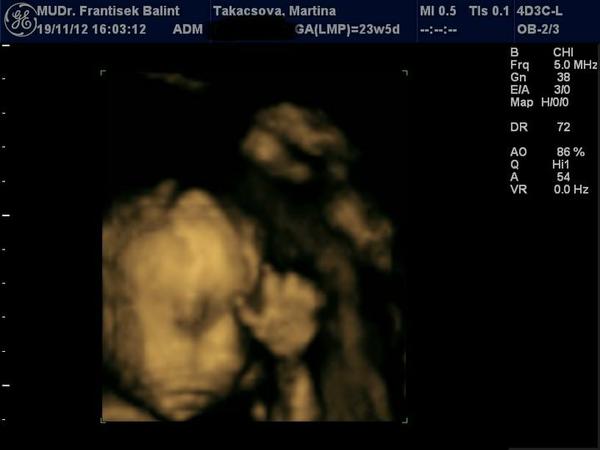

Ahojte kočky. Idem sa s vami podeliť. Včera som absolvovala 3D/4D ultrazvuk. Som veľmi šťastná lebo sa ukázalo, že čakáme zdravú princezničku 😵 Malinká sa moc nechcela ukázať a bolo jasné, že sa jej ultrazvuk nepáčil, čo je vidno aj na fotke. Bol so mnou aj manžel, bol to krásny pocit spolu pozorovať ako sa malinká vrtí 🙂